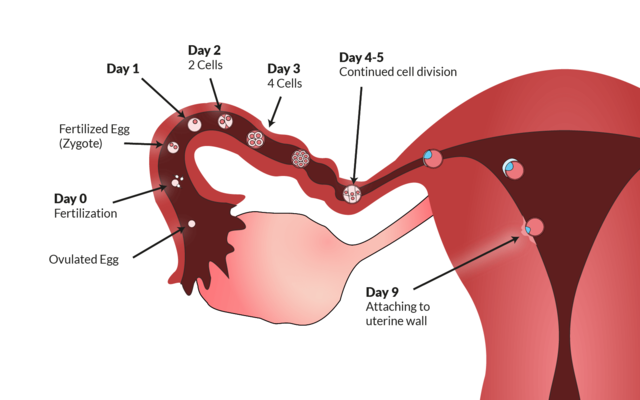

Ovulation- Once a month, approximately every 28 days, the ovary releases ova sometimes it even releases more than one ova.

Conception- The action of conceiving a child or of a child being conceived.

Zygote- A fertilized ovum

• 1st Trimester

Length of Time: Conception - 12 weeks

• 1st Month

1st Month

4 weeks:

1. Baby has heart beat.

2. Baby is developing a heart that pumps blood.

3. Brain is developing.